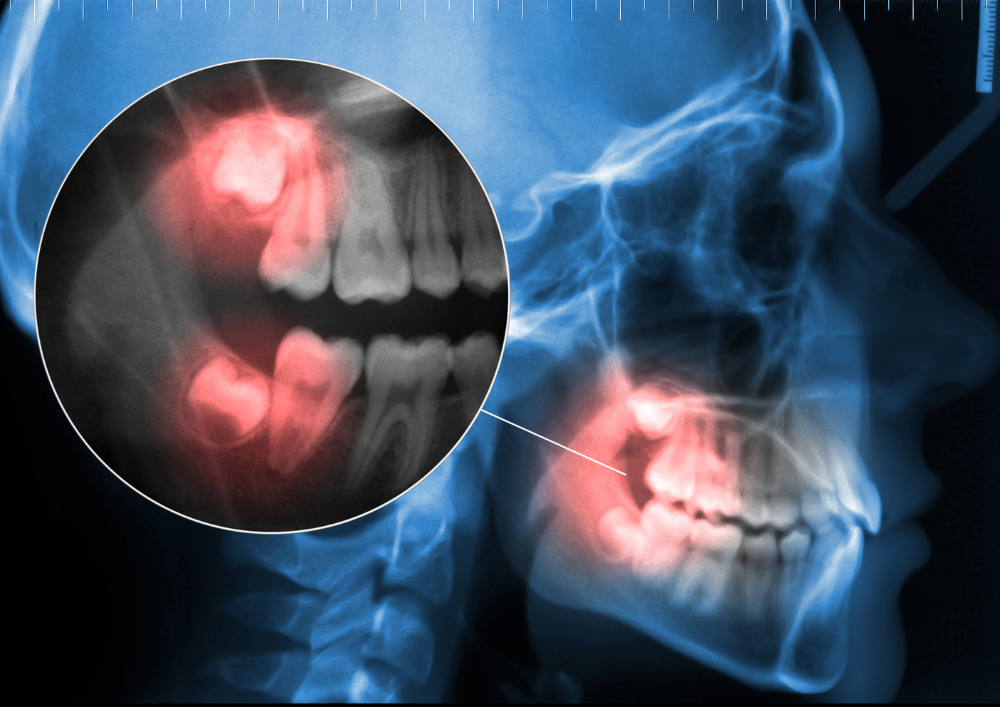

Wisdom teeth usually appear in your late teens or early twenties. Sometimes, they grow in without a problem. But in many cases, they become impacted, grow at an angle, or press against neighbouring teeth, leading to discomfort and even infection. When this happens, the best option is often removal and the sooner, the better.

As a leading dental clinic in Mumbai, we understand how urgent this pain can feel. That’s why we provide quick consultations and, when necessary, same-day appointments for tooth extraction. Our team of experienced dentists uses digital X-rays to accurately assess the position of your wisdom teeth and determine the best treatment.